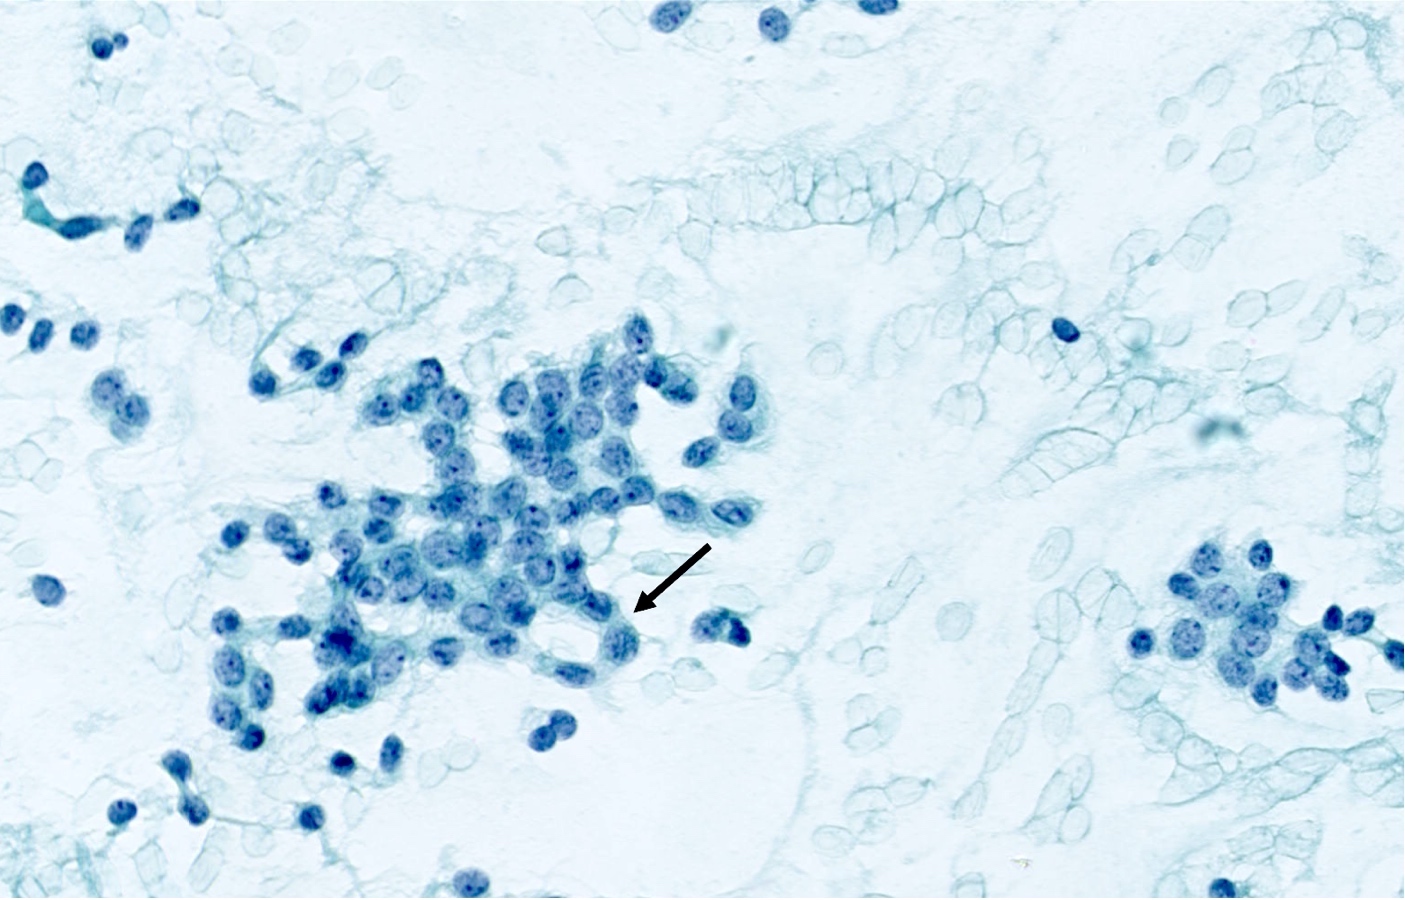

Cytology description

- Loosely cohesive groups and isolated cells sometimes around branching capillaries; rosette structures may be seen (Cibas: Cytology - Diagnostic Principles and Clinical Correlates, 4th Edition, 2014)

- Uniform population of small tumor cells with round / elongated or plasmacytoid shape

- Smooth nuclear outlines, uniform with salt and pepper chromatin and a small nucleolus; no or rare mitoses

- Scant granular cytoplasm

- Absence of molding, nuclear crush and necrosis

Cytology images